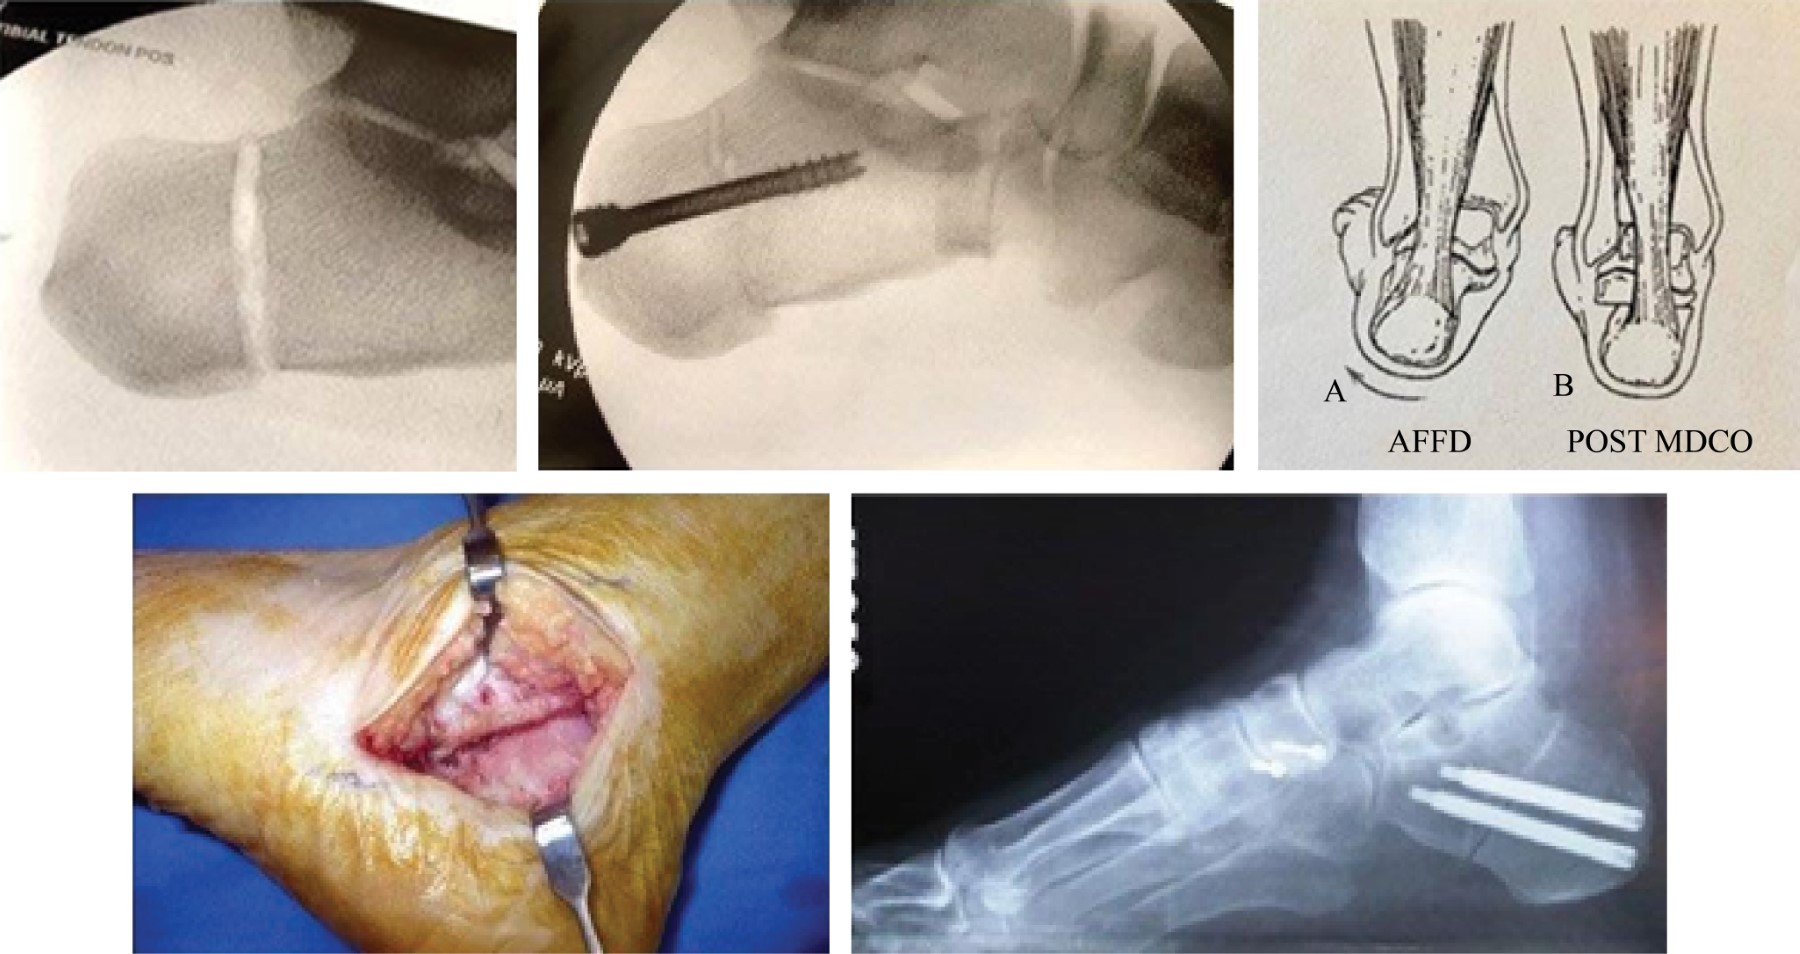

Figure 1

Figure 2

Figure 3

Figure 4

Figure 5

Figure 6

Figure 7

Figure 8

Figure 9

Figure 10

Figure 11